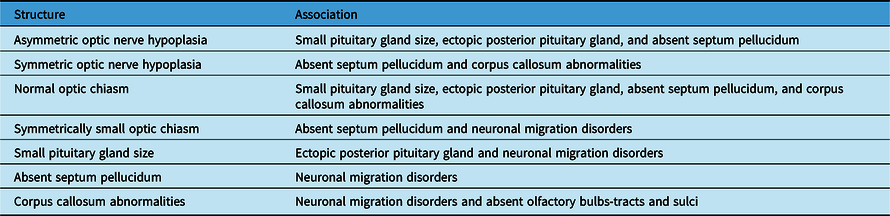

Table 3: Summary of the significant neuroimaging associations

Table 3 shows a summary of the significant associations among structural abnormalities found on neuroimaging in patients with ONH/SOD.

Our study, unlike most other studies, included details on the symmetry in addition to laterality of the reduced optic nerves and chiasm sizes on neuroimaging. The analysis revealed interesting associations among the abnormal neuroimaging features in patients with ONH/SOD (Table 3). As anticipated, both the symmetry and laterality of ONH and reduced chiasm size were concordant, as reported previously. Reference Ward, Connolly and Griffiths20 Symmetric or asymmetric ONH (rather than unilateral ONH), and normal or symmetrically small optic chiasm (rather than asymmetric optic chiasm) were significantly more likely to be associated with other neuroimaging abnormalities. Other studies also reported that bilateral ONH was more likely than unilateral ONH to be associated with: more severe pituitary gland abnormalities and corpus callosum hypoplasia on MRI, Reference Riedl, Vosahlo and Battelino21 and clinical or neuroimaging abnormalities. Reference Mohney, Young and Diehl9,Reference Garcia-Filion, Almarzouki, Fink, Geffner, Nelson and Borchert17 However, some studies reported no association between ONH laterality and the presence of pituitary abnormalities, Reference Qian, Fouzdar Jain, Morgan, Kruse, Cabrera and Suh19 or absent septum pellucidum, Reference Garcia-Filion, Almarzouki, Fink, Geffner, Nelson and Borchert17 on MRI. In general, it appears that unilateral ONH, with or without an asymmetrically small optic chiasm, may potentially have a different etiology from bilateral ONH based on the associated neuroimaging features. This speculation deserves further study.